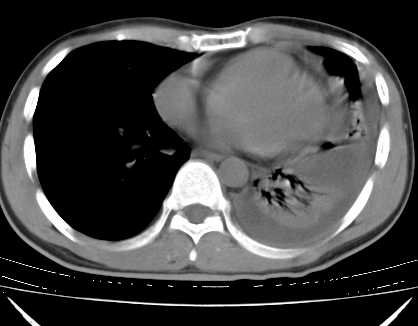

二周前患者无明显诱因出现咳嗽,多为刺激性干嗽,无咯血,伴心悸,低热,夜间无明显盗汗,消瘦明显

年龄?左侧胸腔中量积液,左下肺见有较多斑片状和大片状影,伴有支气管充气征,考虑:1、左下肺炎;2、结核。肿瘤可以基本排除。

考虑:1、左下肺结核左侧胸腔中量积液,心包积液纵隔肿大淋巴结.

考虑:1、左侧中量胸腔积液伴左肺下叶肺膨胀不全、炎症。

2、心包积液。

左下肺见有较多斑片状和大片状影,支气管通畅,左侧胸腔积液,考虑:左下肺炎伴胸腔积液

1、左侧中量胸腔积液伴左肺下叶肺膨胀不全、。

左肺舌叶及下叶见斑片状,大片状高密度影并相应处胸膜及心包不规则增厚,左肺下叶膨胀不全。右肺未见异常,双肺段以上支气管通畅。纵隔左移,其内未见明显肿大淋巴结。左侧胸腔积液。

1.考虑:左肺化脓性炎症。2.左侧胸腔积液(中等量)。3.心包炎症。